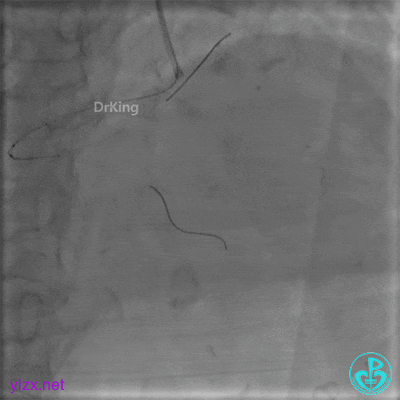

远段造影剂外渗在增加,怎么办?

微导管送入PL分支远段,取明胶海绵颗粒栓塞剂1ml通过微导管向远端血管推注栓塞远端血管。

封堵后造影,PL分支远端血流中断。